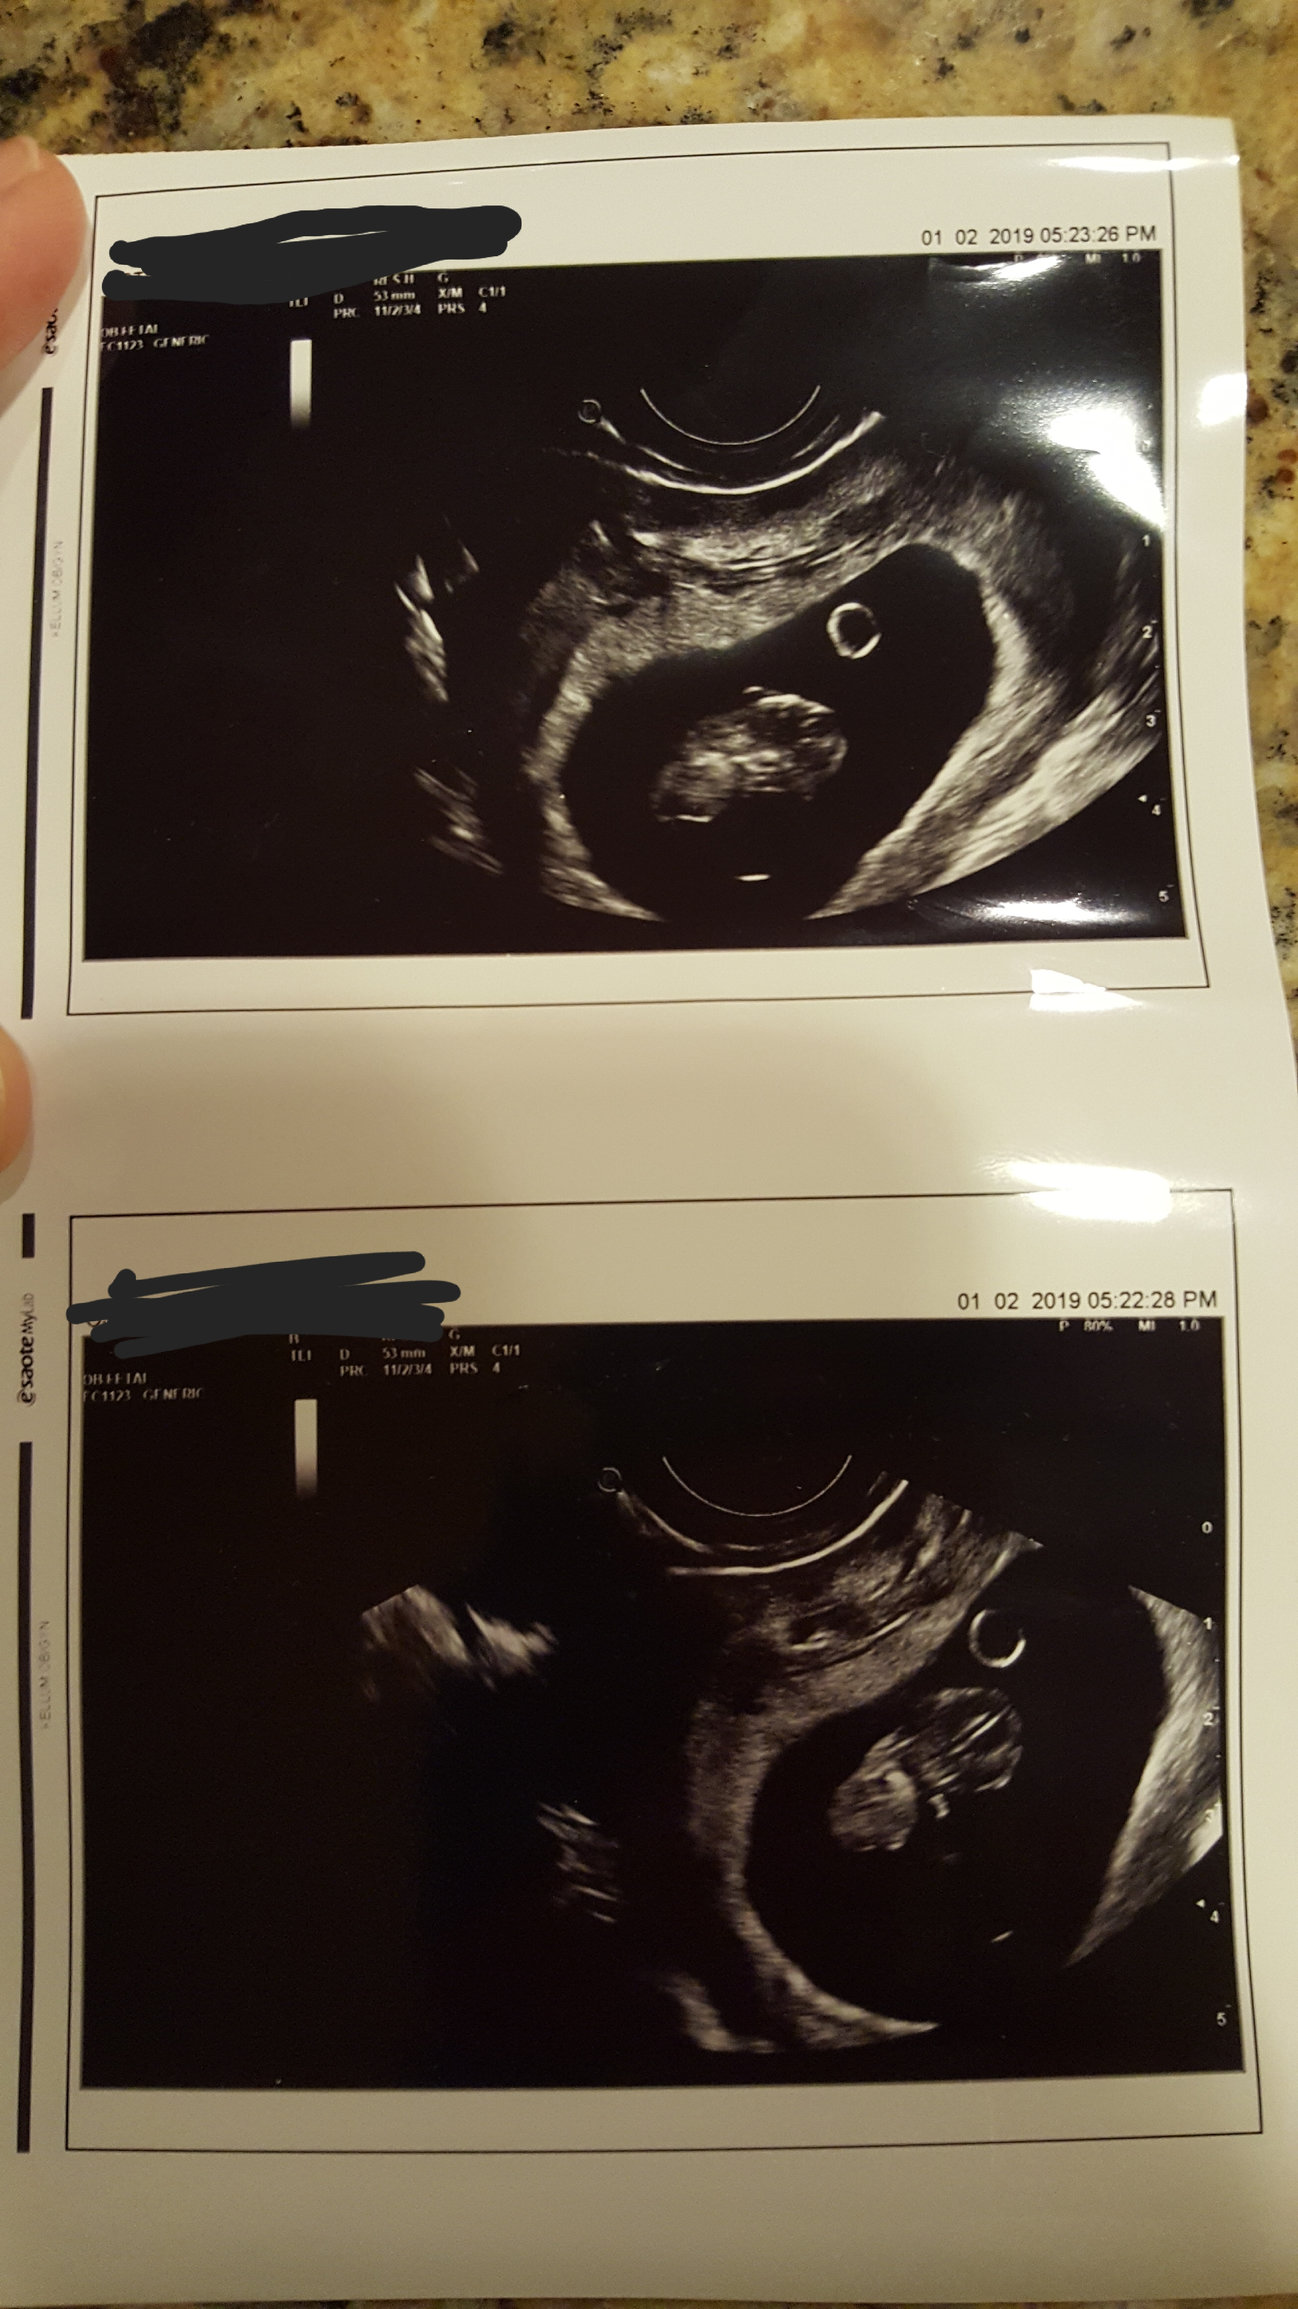

First u/s today at 6w4d. Honestly this early it’s just all blobs to me but my dr diligently showed us the flutter of the HB and also had us listen. I think HB was clocked at 138. Here’s the pic with sound waves. I think the print out said measuring 6w1d but my dr said the embryo was measuring at .4 cm and anything between .25 and .5 would be just right.

First u/s at 6+3. We weren’t told the exact HR, though everything is measuring on time.